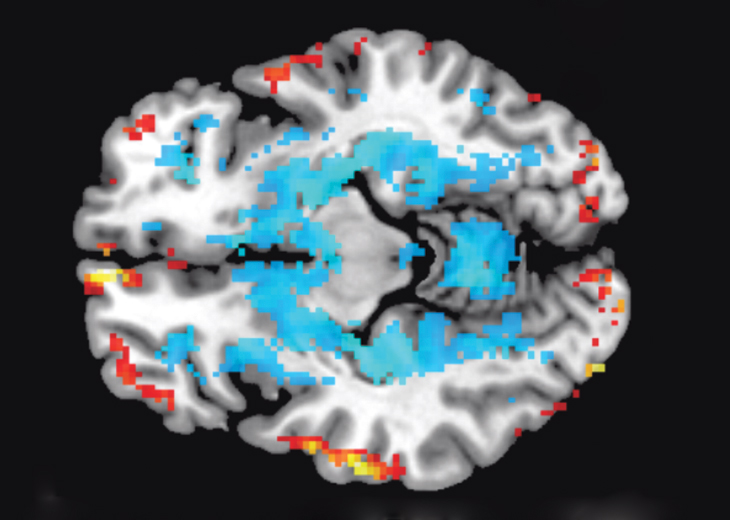

OLD TECH Two techniques using magnetic resonance imaging, or MRI, have already made progress in mapping the physical connections (fibers of white matter) linking various parts of the brain and in identifying regions that are active during specific tasks.

Magnetic resonance imaging, or MRI, allows scientists to get good anatomical maps of the whole brain and broad activity patterns (SN: 12/19/09, p. 16). But as good as it is, MRI technology still misses lots of detail. A million neurons can reside in a single voxel, the smallest unit that functional MRI can detect. “MRI shows you wonderful neuroanatomical details, fantastic, but it does have a resolution limit,” Ling says. “How can we increase it? Easy — build a bigger magnet. Oh, good, let’s have a 50 Tesla magnet. What city are you going to put this in? Because you have to wipe out about seven blocks to do it.” Supersizing existing technology won’t work, Ling says. Fundamentally new ideas are needed.